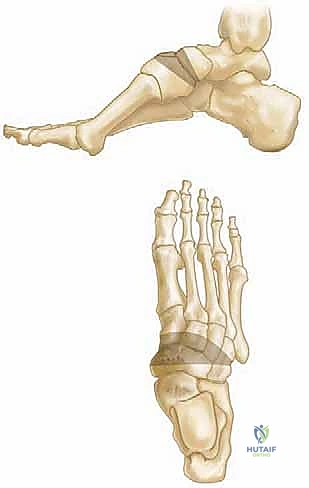

لفهم مشكلة القدم الجوفاء، يجب أولاً فهم الهندسة المعمارية للقدم البشرية. تتكون القدم من 26 عظمة، و33 مفصلًا، وشبكة معقدة من أكثر من 100 وتر وعضلة ورباط. تعمل هذه المكونات معًا لتشكيل ثلاثة أقواس رئيسية (قوسان طوليان وقوس عرضي) تعمل كنوابض لامتصاص الصدمات وتوزيع وزن الجسم.

في حالة القدم الجوفاء (Cavus Foot)، يحدث خلل في التوازن العضلي، غالبًا ما يكون ناتجًا عن ضعف في العضلات الجوهرية للقدم مقابل نشاط مفرط للعضلات الخارجية (مثل العضلة الظنبوبية الخلفية والشظوية الطويلة). يؤدي هذا الخلل إلى:

1. انثناء أخمصي في المشط الأول (Plantarflexed First Ray): مما يدفع القوس للارتفاع.

2. انقلاب الكعب للداخل (Hindfoot Varus): مما يقلل من مساحة التلامس مع الأرض ويسبب عدم استقرار الكاحل.

3. أصابع المطرقة أو المخالب (Claw Toes): نتيجة الشد المستمر للأوتار الباسطة والقابضة.

* قطع عظم المشط الأول (First Metatarsal Dorsiflexion Osteotomy): إزالة إسفين عظمي صغير لرفع المشط الأول وتقليل القوس.

* قطع عظم العقب (Calcaneal Osteotomy): تحريك عظمة الكعب إلى الخارج (Lateralization) لتصحيح الانقلاب الداخلي (Varus) واستعادة استقرار الكاحل.